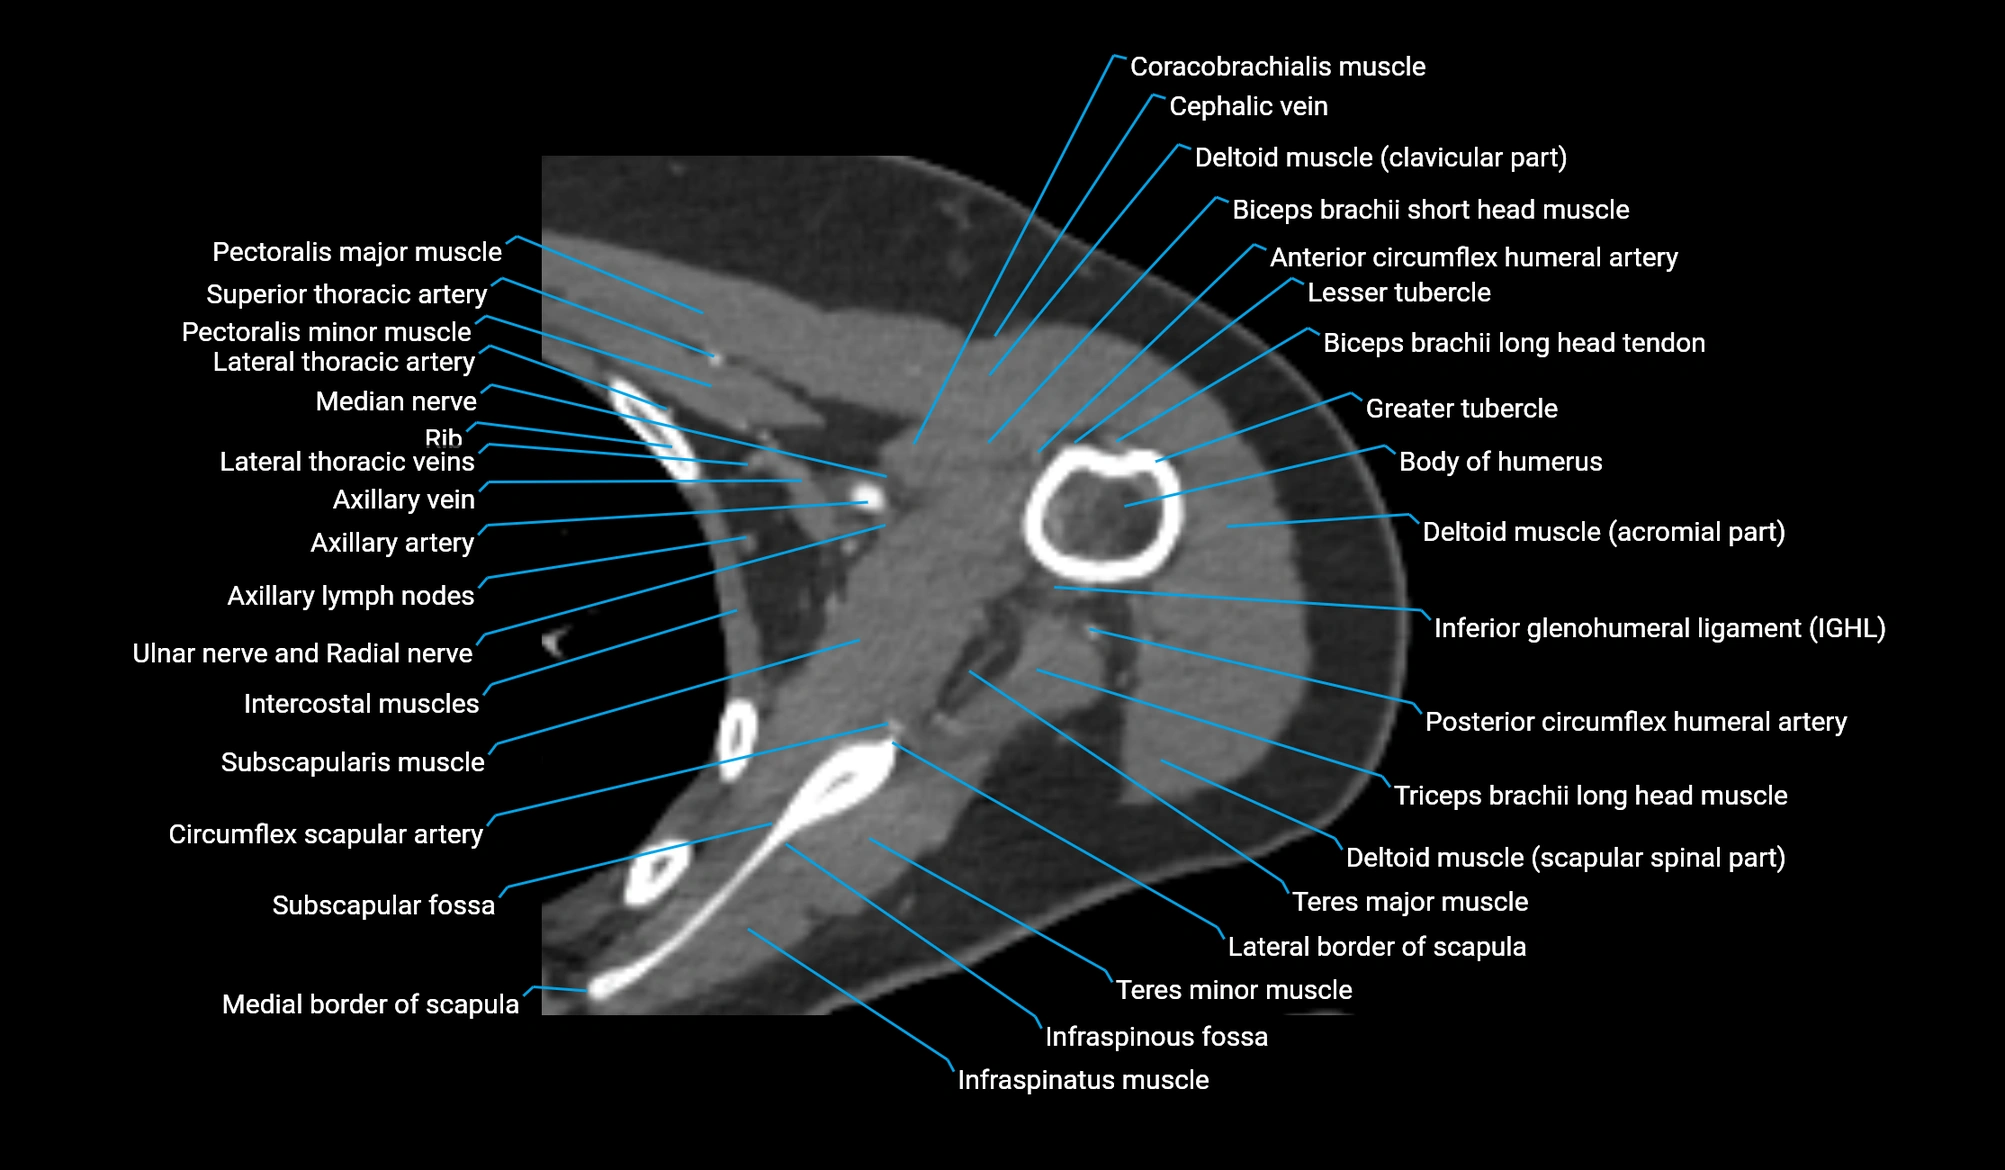

CT image